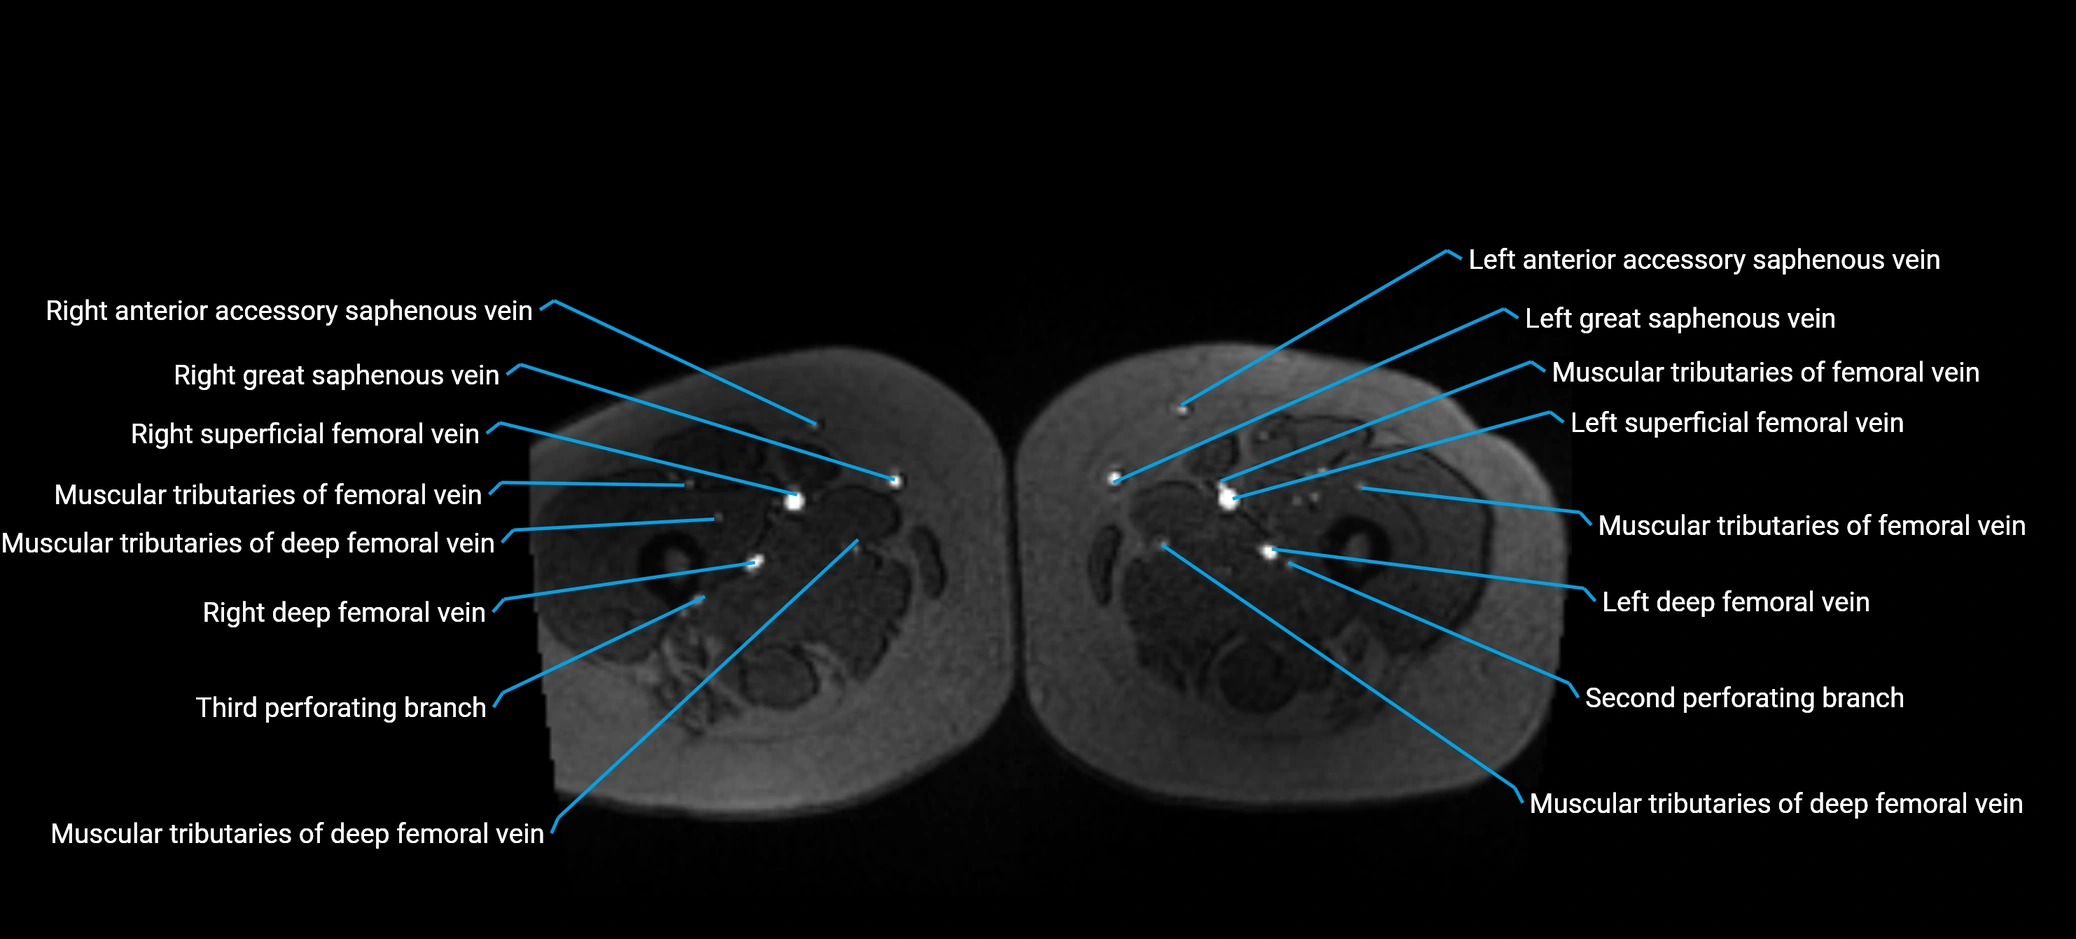

MRI image

image